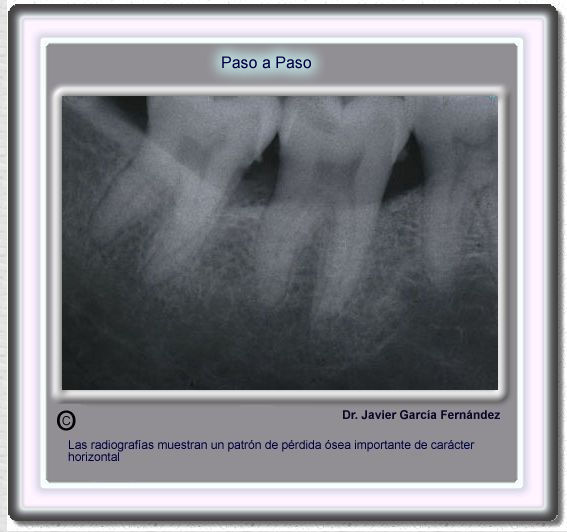

image 467